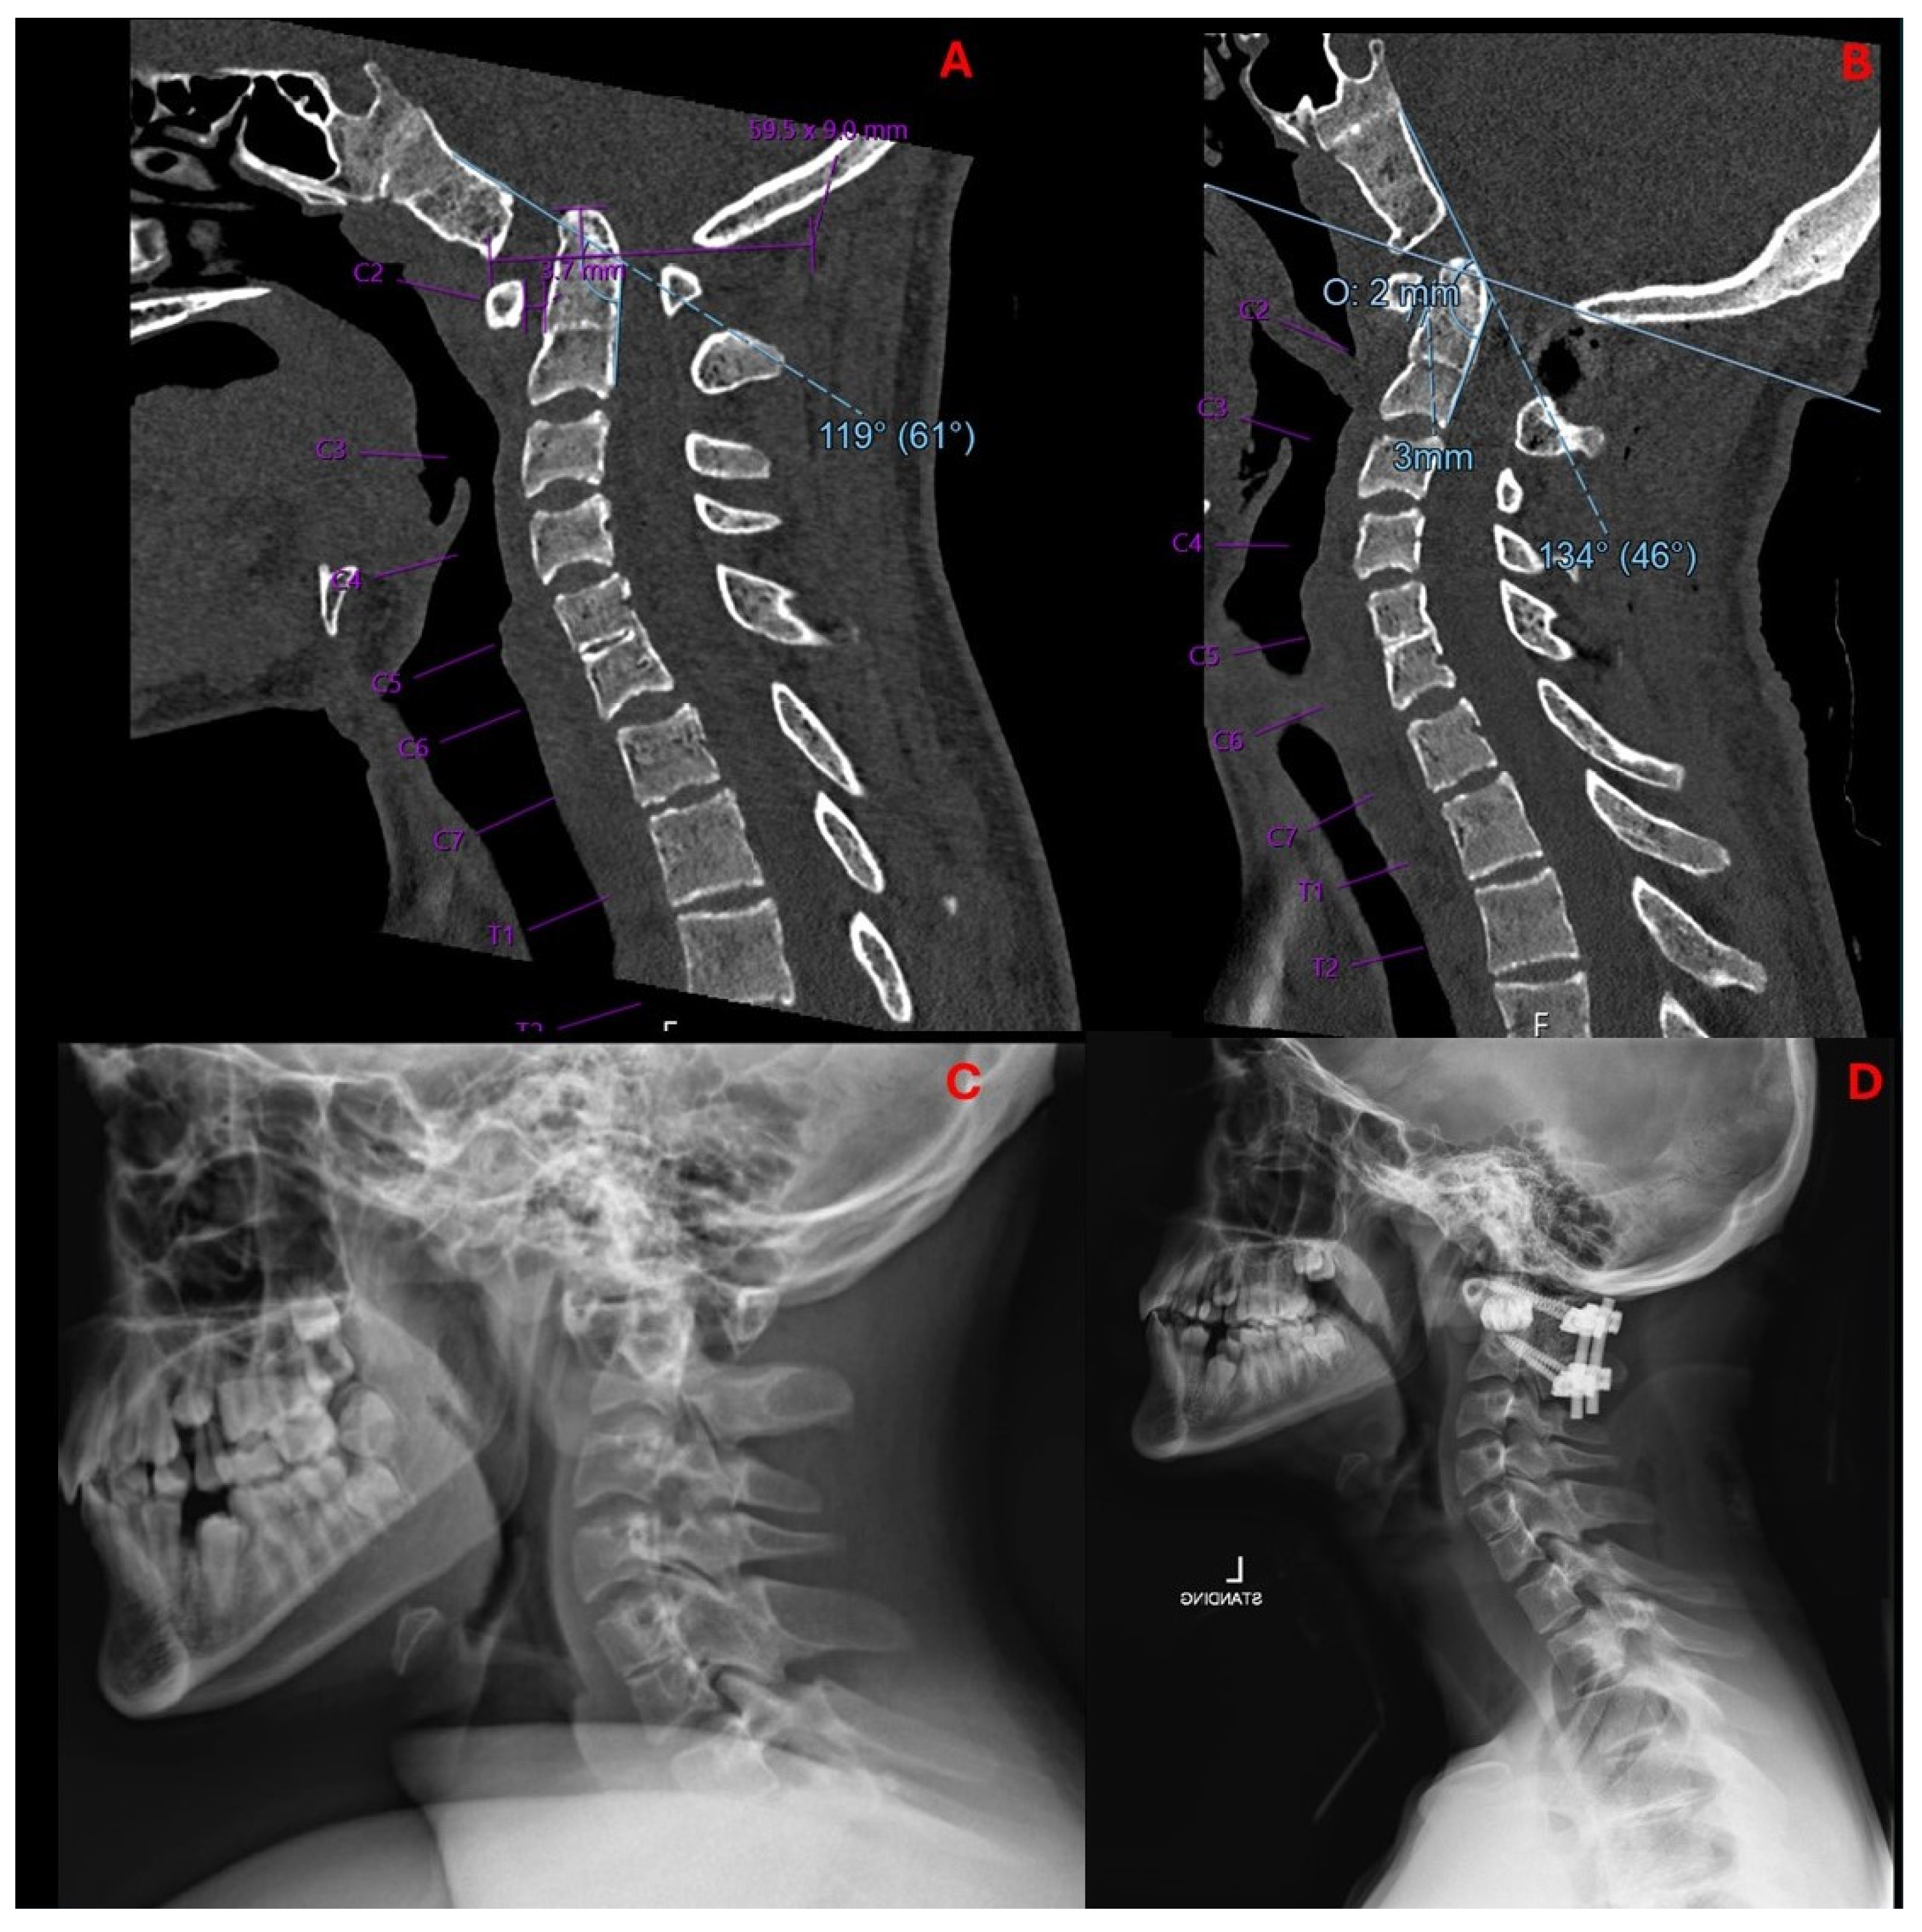

2.2. Imaging and Diagnosis

3.1. Preoperative Planning and 3DPI Design